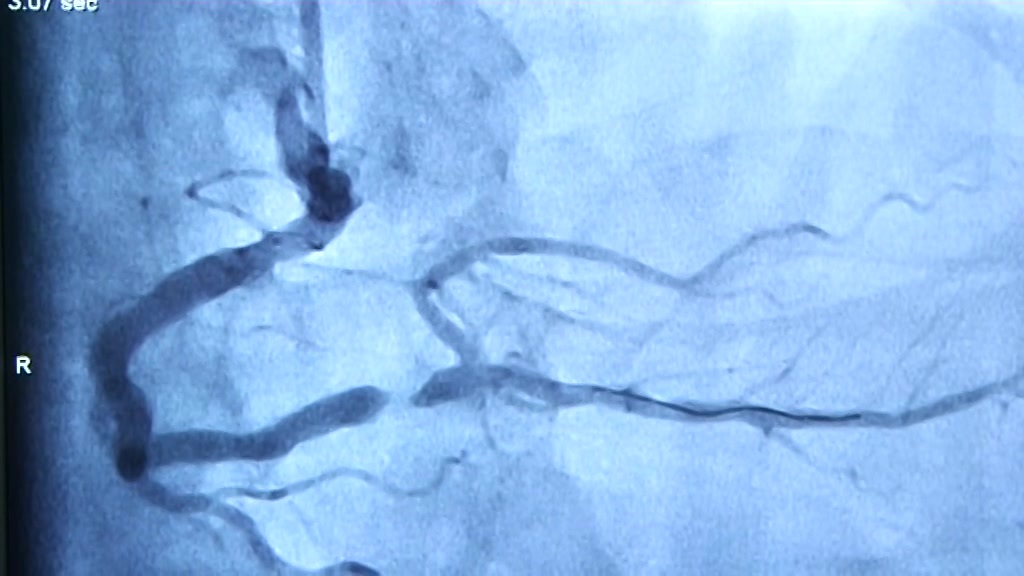

Es fängt meistens mit einem diffusem Druck in der Brust an. Daraus wird dann ein Brennen bis hin zu starken Schmerzen. Vom harmlosen Anfang bis zum Kampf ums Überleben. Die Rede ist vom Herzinfarkt. Patienten schildern, dass sich Minuten wie Stunden anfühlen. Immer dabei, die Angst zu sterben. Und die ist mehr als berechtigt. Der Herzinfarkt  gilt immer noch als zweithäufigste Todesursache in Deutschland. Nur schnelles Handeln kann da helfen.